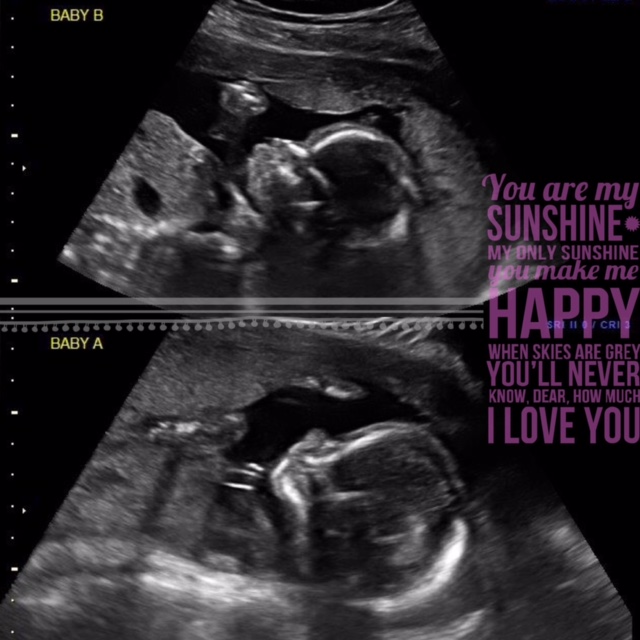

U/S yesterday and we have 2 healthy little girls! They're laying like they're in bunk beds with their heads on opposite sides. It's still so crazy to me that there's 2 tiny little people in there!